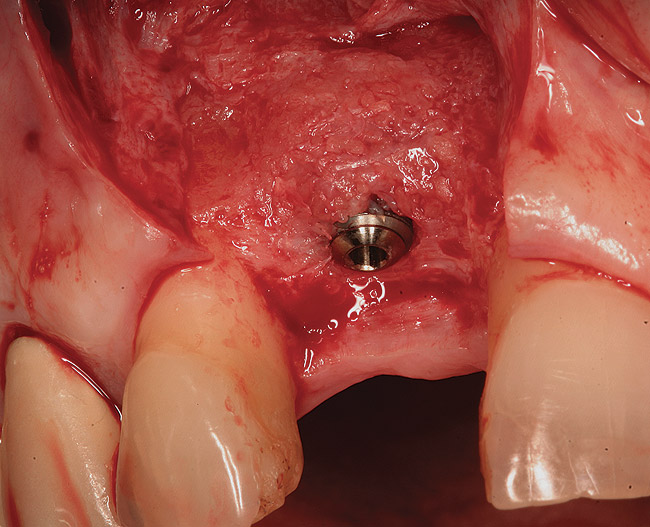

Figure 3  (Case 1) Removal of implant was accomplished using piezo-surgery in order to maintain the lingual plate. Note that trephines are not recommended for this procedure.

Figure 3